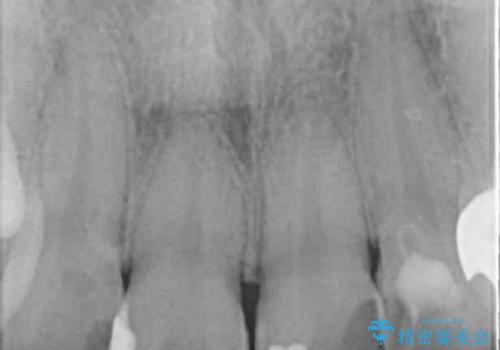

特に裏側のつぎはぎ、二次う蝕(治したところの境目からの虫歯)が多く、審美目的だけでなく、虫歯の治療としても意味があったと思います。

神経を温存するようにあまり削らないように治療しました。